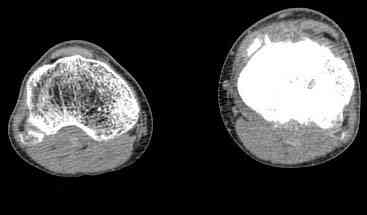

важаемые коллеги! Поступил больной 22 лет. Болен с января 2006 - появились боли в области верхнейтрети голени. При первичном осмотре в поликлинике был заподозрен первично-хронический остеомиелит - осмотрен гнойным хирургом - произведена биосия . Заключение - хондросаркома. Осмотрен онкологом - с учетом характера опухоли - химиотерапия, лучевое лечение не показано. Предложена либо ампутация, либо решение вопроса о возможности выполнения органосохраняющей операции. При обращении к нам произведена сцинтиграфия скелета - зоны гиперфиксации РФП: верхняя треть голени- 960%, нижняя треть бедра - 380%, Дистальный метафиз голени и затылочная область - 140%. В легких - метастазов нет. Произведена КТ (картинки в приложении). Учитывая абсолютную нестыковку рентгенологических и морфологических данных повторно биопсия. Выявлено, что первичная биопсия выполнялась из поверхностной параоссальной зоны - там локализованы хрящеподобные массы, далее очень плотная кость без хрящевых участков - биоптат взят фрезой с большим трудом. Морфологического заключения пока нет. Хотелось бы узнать Ваши варианты диагноза и соответственно тактику.

Не специалист по онко ортопедии, но по локализации (бедро, большеберцовая и плечевая кость), возрасть, в данный момент отсутствия метастаза и формация новой кости с мягкотканним вовлеченим, процесс больше напоминает остеосаркому большеберцовой кости.

Припухлость над опухолью и кожные изменения, подобно воспалительной и боли при нагрузке могут быть приняты общими ортопедами как остеомиелитический процесс.

Биопсия затрудняется из-за склероза, онко ортопеды пользуются для биопсии специальным набором режущих игл.